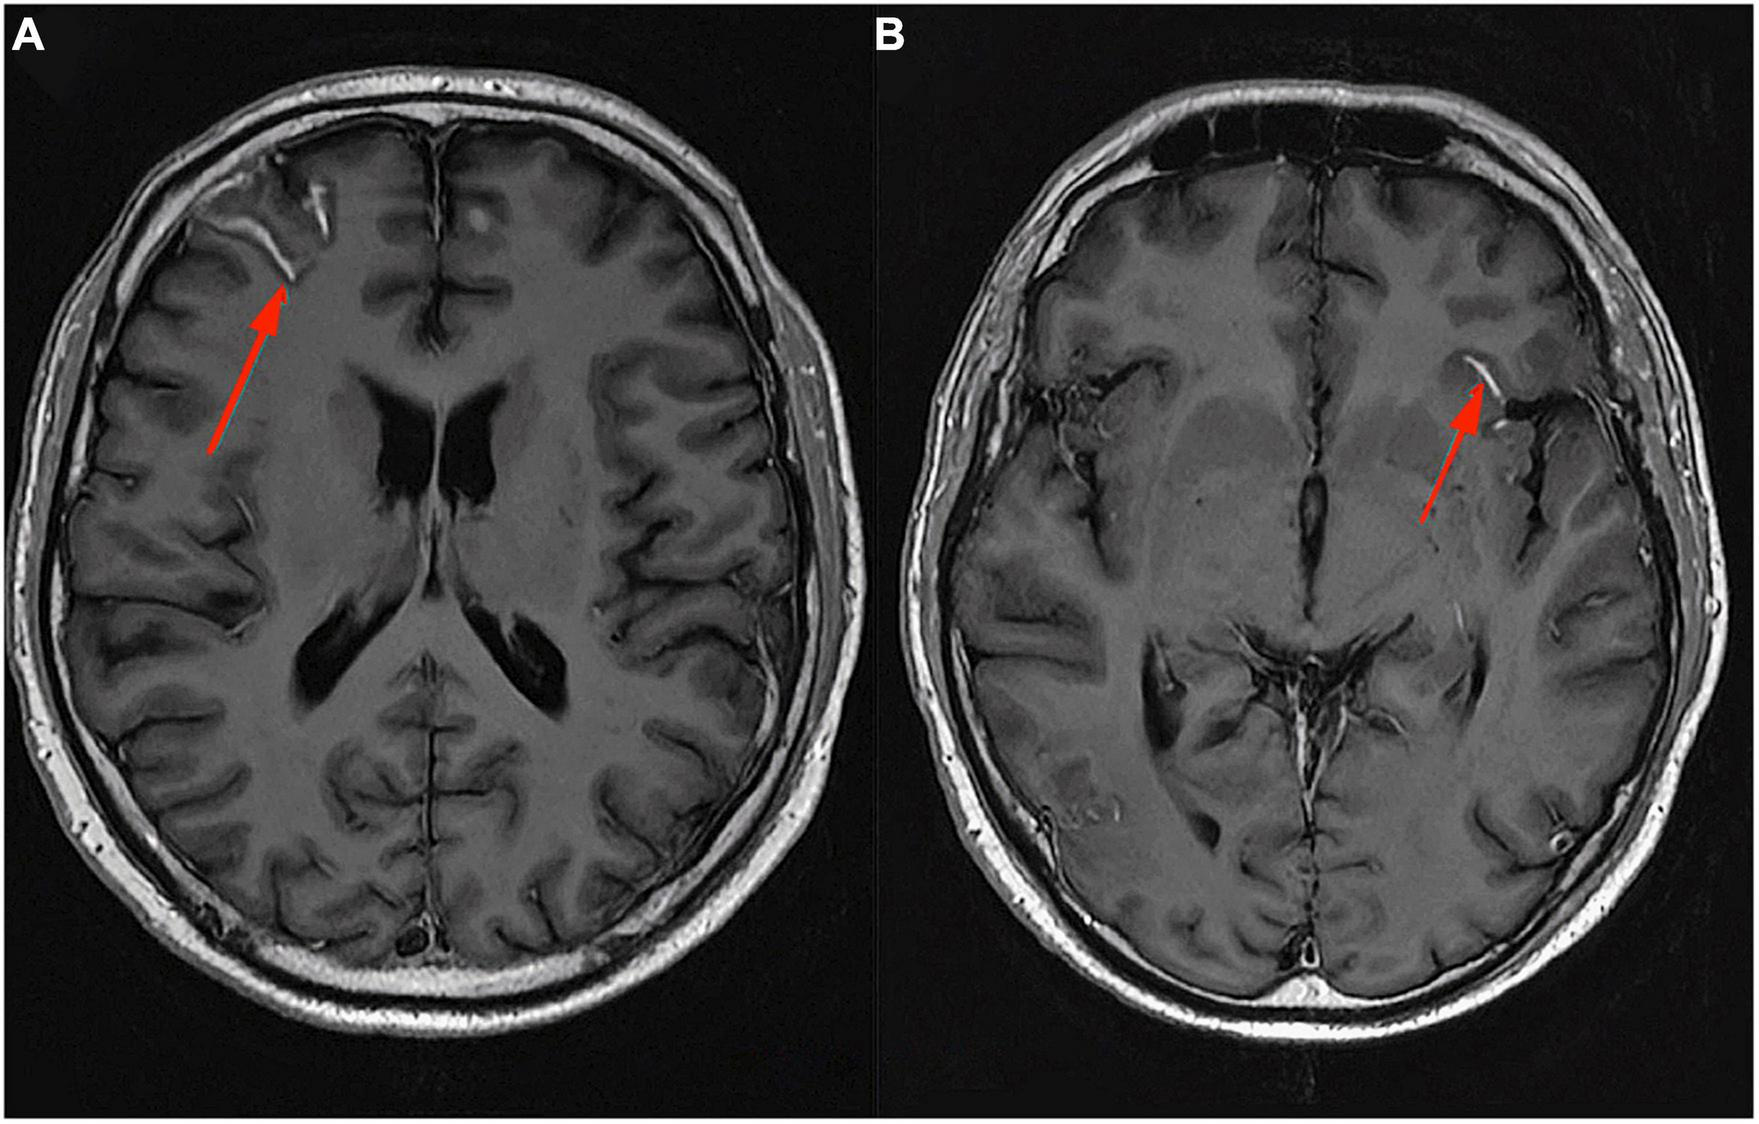

In conclusion, pro-inflammatory macrophages/microglia in SELs may or may not contain iron deposits, while the presence of specific iron-rich rims is a strong indicator of the pro-inflammatory status of microglia or macrophages. Furthermore, no iron rims were observed around most of the “plaque shadows”; this may indicate that remyelination is limited to lesions that never underwent rim iron accumulation. These findings suggest that the occurrence of iron rims in MRI images of the brains of MS patients could indicate progressive tissue deterioration. In addition, the presence of a higher number of iron-margined lesions is associated with more frequent clinical relapses and their association with clinical disability suggests that they might also constitute a risk factor for clinically progressive disease development. An MRI image, SWAN sequence, of a typical iron rim in a patient with SPMS is presented in Figure 2; the patient is under the care of the Neurological Clinic of the Military Medical Institute–National Research Institute.

FIGURE 2

MRI Swan sequence, axial section. Iron rim sign in a patient with SPMS (A–C). Material from the resources of the Medical Radiology Department of the Military Medical Institute–National Research Institute.